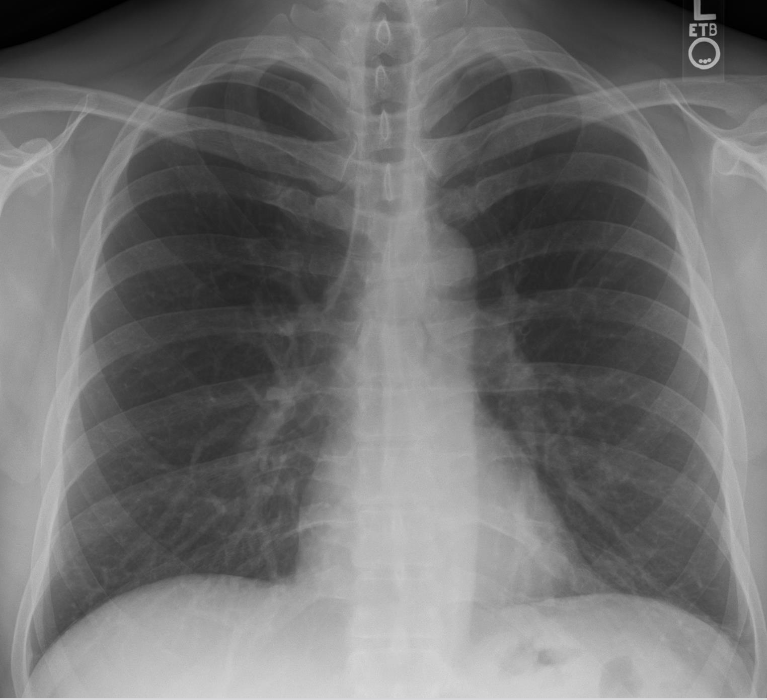

how does radiography work?

x-ray source on one side of patient & x-ray detector on the other side

short duration (<1.2 second) pulse of x-rays is emitted by the tube

most rays interact with the patient

some pass throught the patient and reach the detector

what causes a heterogeneous pattern of x-rays reaching detector?

different attenuation patterns of tissue